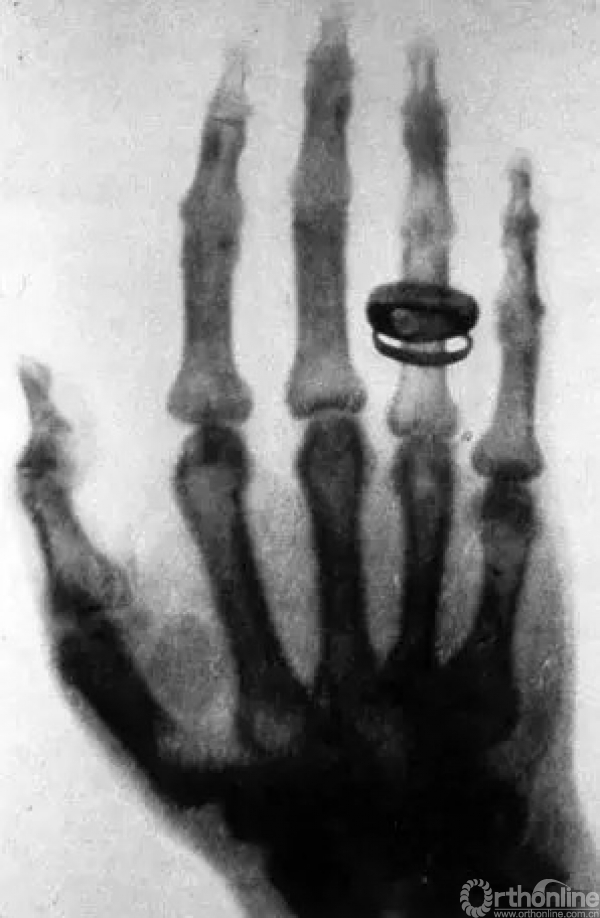

1895年,伦琴发现了X线。同年12月22日,伦琴给他太太拍摄了手部的X线片。这是第一张人体X线摄影,手指上那个黑咕隆冬的物体是婚戒。之后不久,X线就开始应用于医疗。